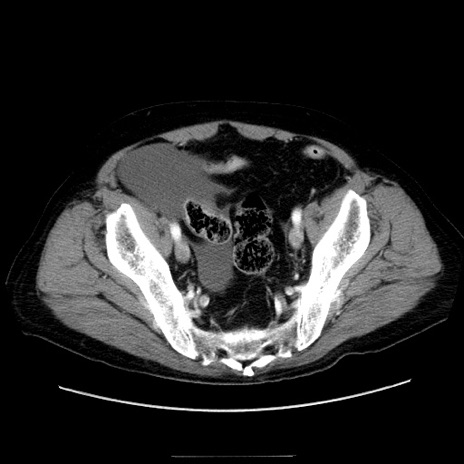

冠状断像

症例30(横断像)

【症例】80歳代男性

【主訴】臍周囲痛

【現病歴】約6時間前から臍下部痛が出現。次第に腹部膨隆・背部痛も生じてきたため来院。背部痛の場所は変化しない。

【身体所見】意識清明、BT 36.3℃、BP  131/87mmHg、P 87bpm、SpO2 100%(RA)、臍周囲自発痛・圧痛あり、反跳痛なし、自発痛部位に一致して板状硬あり、腹部膨隆、腸雑音減弱、CVA tenderness両側陰性。

【データ】WBC 19600、CRP 0.33